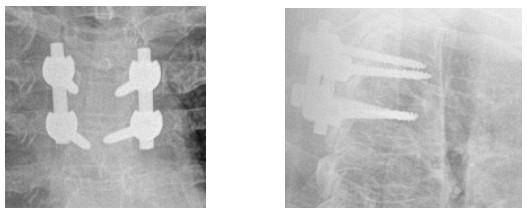

10歲小孩術(shù)前增強MR

術(shù)后復(fù)查不固定位置良好